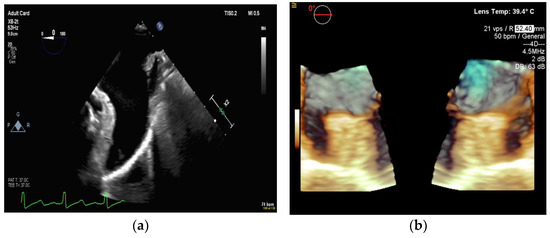

4.2.1. Transseptal Puncture